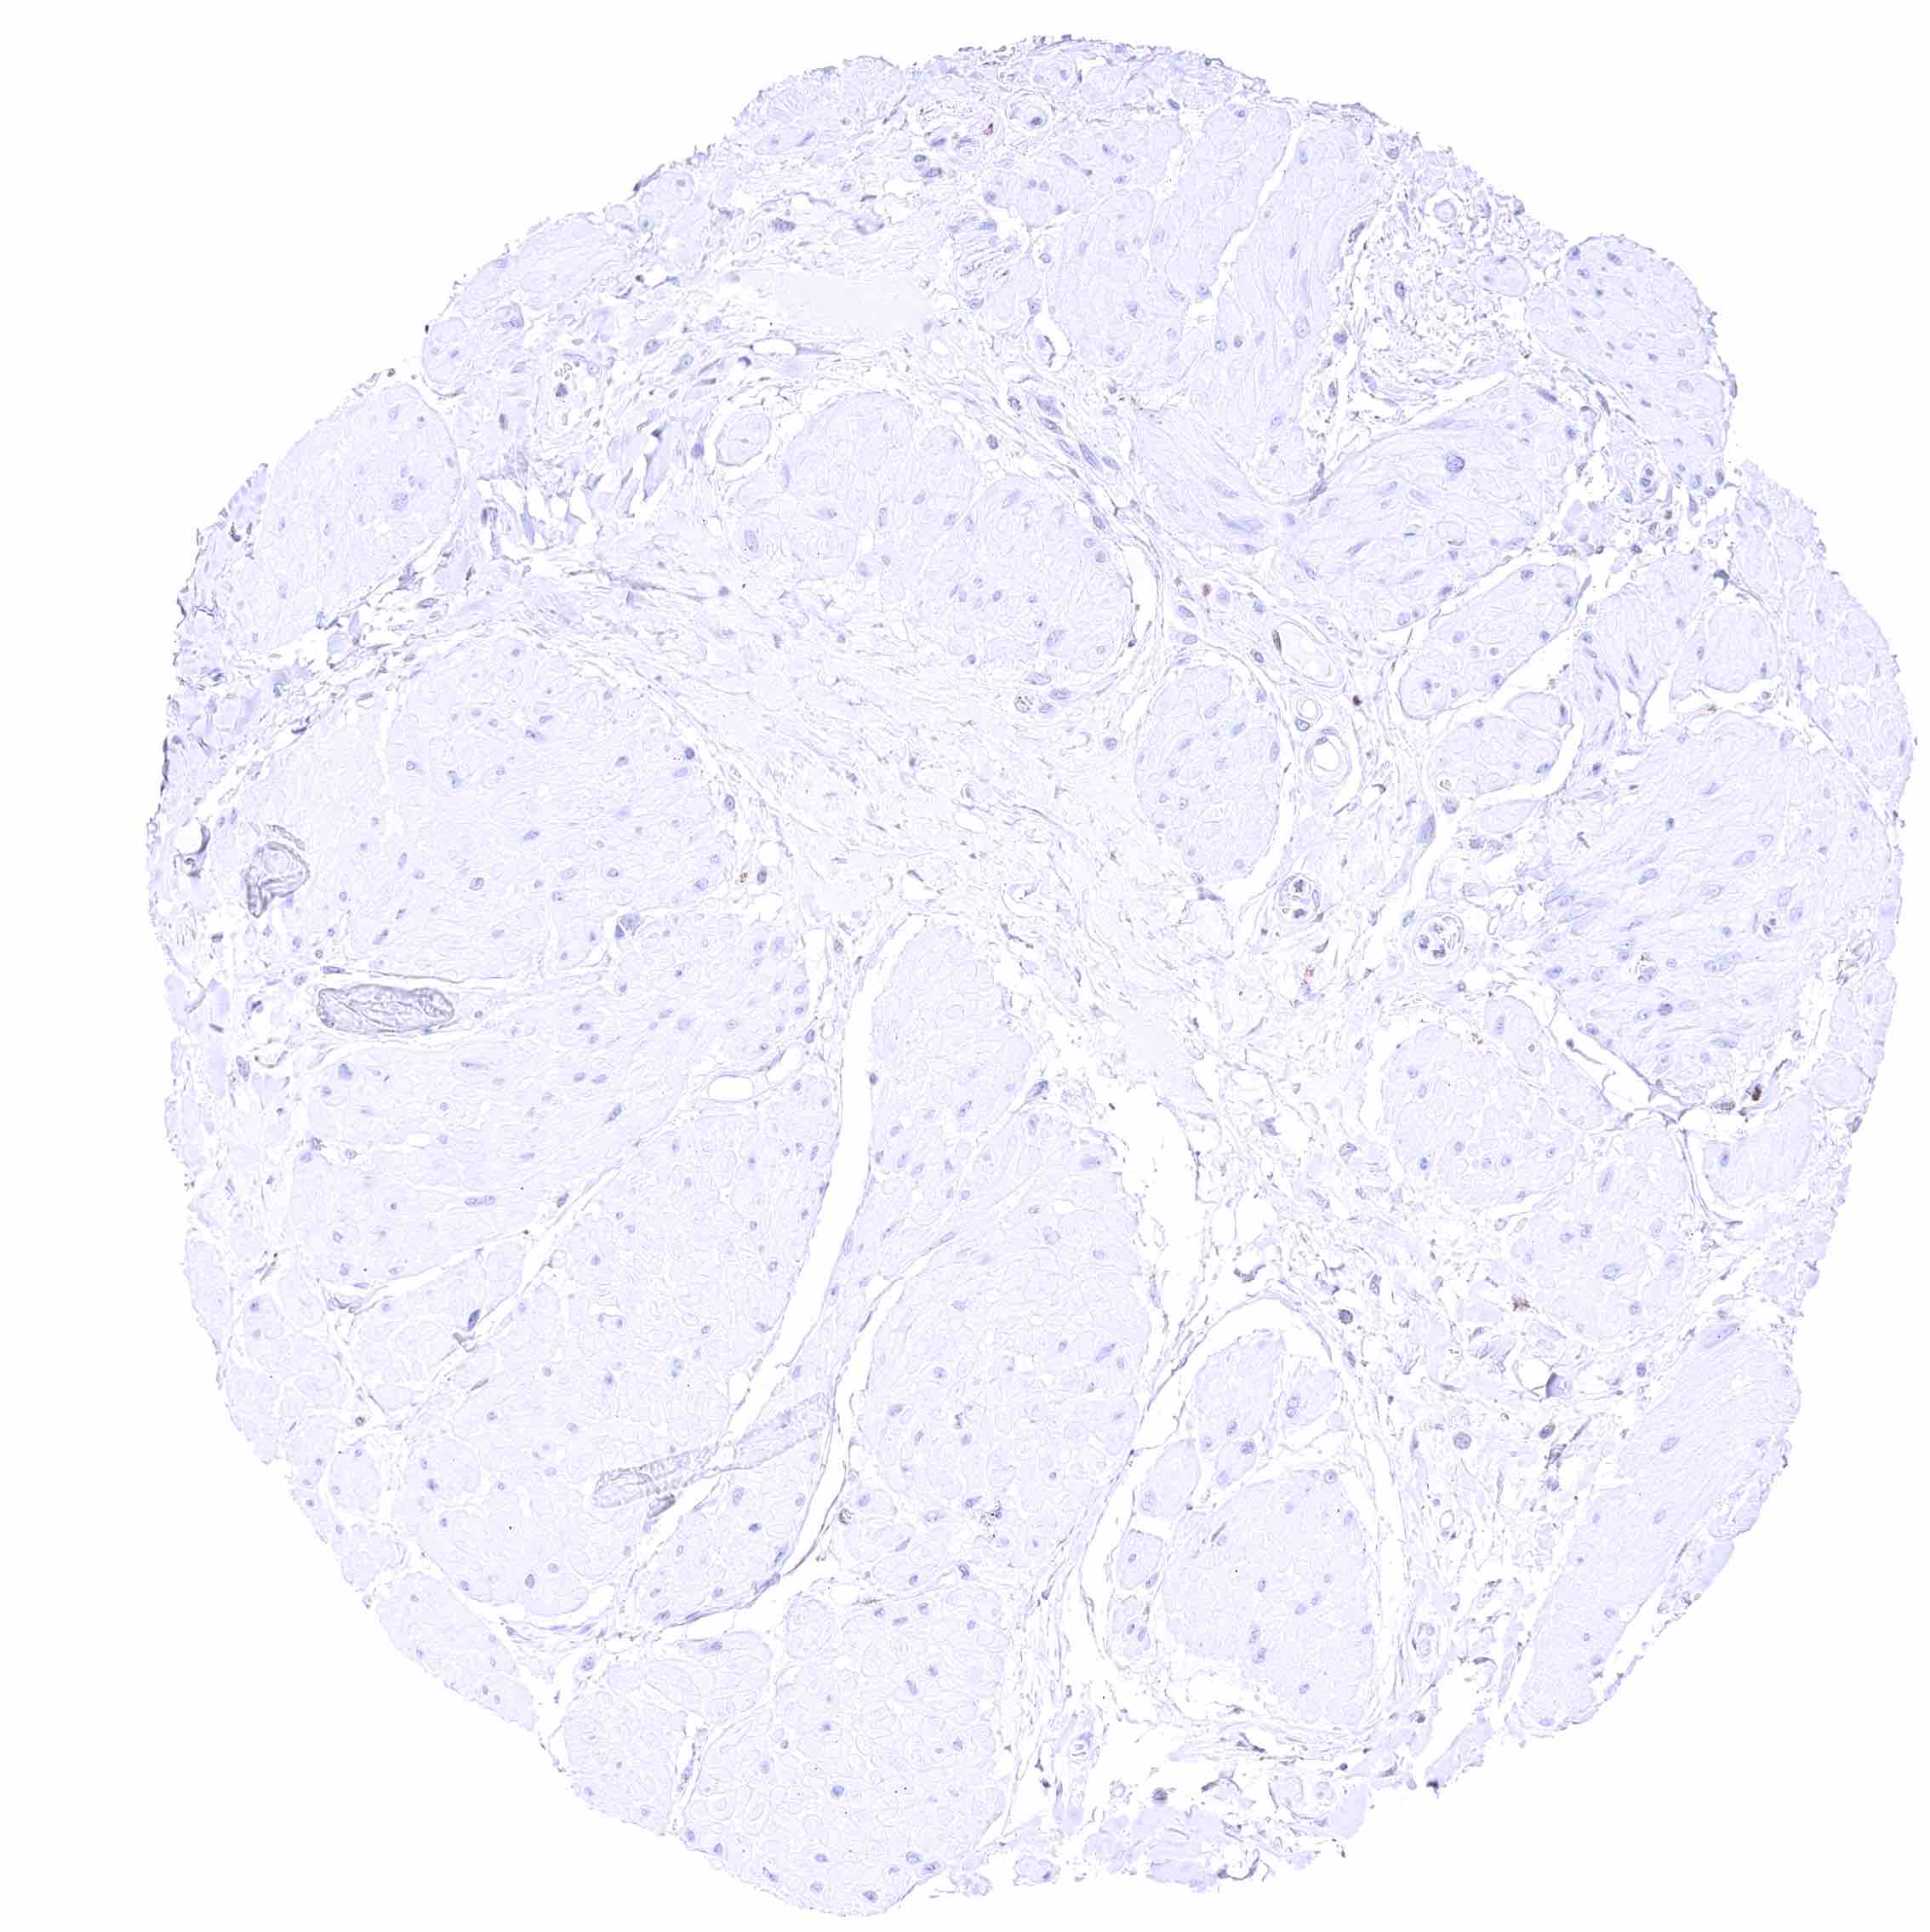

Prostate – Weak to moderate, nuclear GATA3 staining of basal cells. .jpeg